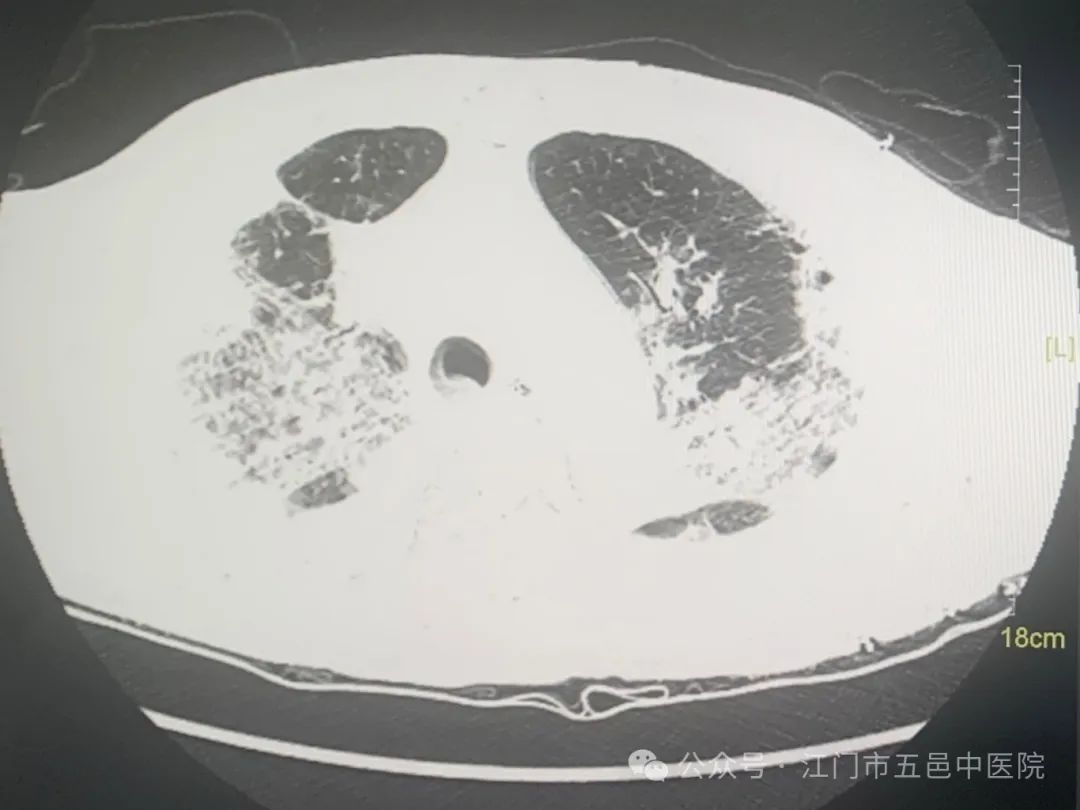

基于以上原因张伯转至江门市五邑中医院肺病科专科诊治,他的疾病很快得以确诊,检查提示为甲型流感。在医生为张伯治疗期间,他的病情却迅速恶化,一度出现呼吸窘迫,呼吸频率达每分钟41次,胸部CT检查显示其双肺大面积变白,也就是“白肺”患者!

病人的血氧饱和度一般需要在95%以上才能称得上安全,可他在无创呼吸机高参数支持下只有80%多。科室医生立即为张伯行气管插管、有创呼吸机辅助通气,并增加肺保护治疗。重症“白肺”患者,死亡率在40%以上。张伯需要通过呼吸机百分百纯氧气送入肺内,才能维持生命所需要的氧气消耗。